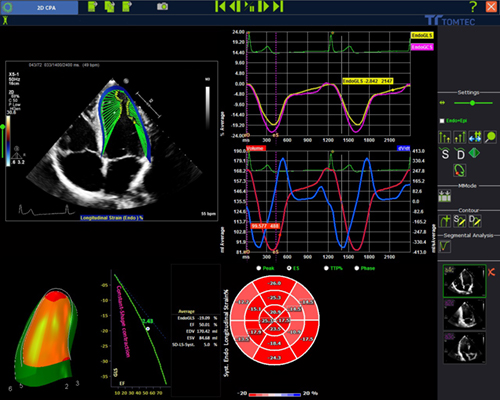

・Strain解析機能を一新した心エコー画像解析システム

「心エコー画像解析システムTomTec-Arena」